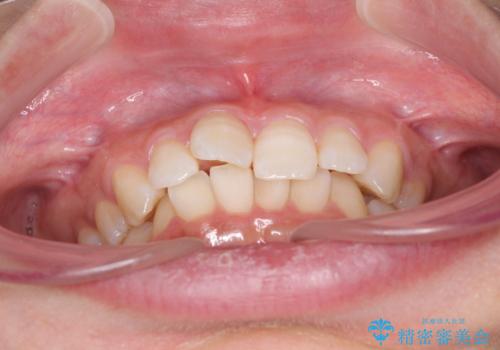

- 前歯のデコボコと奥歯の不正咬合を気にして来院された患者様です。

左右の大臼歯が全て鋏状咬合(シザーズバイト)になっており、治療が難航することが予想されましたが、インビザラインにより治療を行うこととしました。